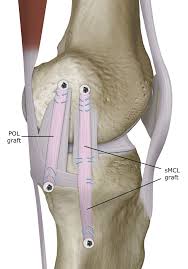

The repair work can be done in 1 of 2 ways: Tendon from another area may be. An mcl graft can be.

Treatment options for an mcl sprain. The surgery will either repair or reconstruct the mcl. A total rupture of the mcl usually doesn’t require surgery.